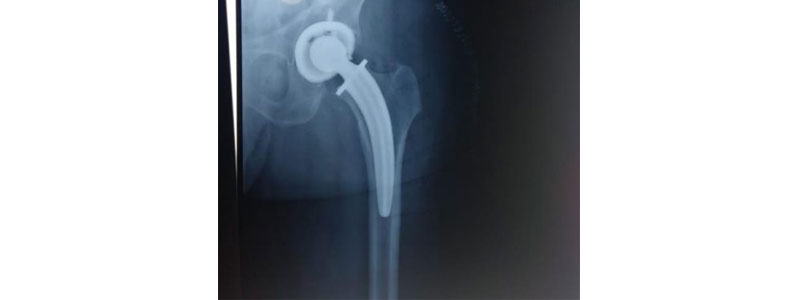

Dr. Chetan Wankhede is Consultant Orthopedic Surgeon and one of the leading Hip Replacement Surgeon in Thane. A hip replacement is a sort of a surgery wherein a declined hip is supplanted with a fake metallic joint.

Total hip replacement is a method that replaces the exhausted or harmed hard finishes of the joint attachment and the chunk of the femur with a Prosthetic Hip (counterfeit joint) produced using biocompatible demonstrated materials which don't respond in body (tissue) materials.

As per Hip Replacement Surgeon in Thane, these materials utilized in the hip restoration surgery are latent and have demonstrated amazing outcomes. At Thane we offer sympathetic consideration which includes picking the right sort of prosthesis (contingent upon different variables like age, sex, bone mineral thickness, and femoral life structures and so on.). Our Hip Replacement Surgeon In Thane generally favor the best concrete less embed which is made of demonstrated titanium metal. The bundle of the embed is made of fourth era current inserts with life span against destroying to thirty years. The other biocompatible materials are additionally utilized like metal - Cobalt-Chromium, Oxinium; the past plastic attachments have been obsolete and by and by profoundly cross-connected polythene (plastic) attachments are being utilized for patients which have life span against wear up to 15 to 20 years.

In complete hip replacement both head of femur bone and attachment of hip bone socket is changed. Different choice in surface: Metal on metal/metal on poly/fired on poly/earthenware on ceramic. In physical THR there is negligible bone cut with protection of neck and furthermore short bended physical stem.

Depending on the patient's age, needs and health, the damaged femur and hip sockets are removed and replaced with ceramic, metal or plastic components during total hip replacement (THR). Doctor Chetan Wankhede is known as one of the hip replacement surgeon in thane. Patients with degeneration of the cartilage of the hip joint undergo total hip replacement (THR). Total hip replacement surgery is recommended for patients whose hip joints have been so deeply damaged by osteoarthritis that repositioning the hip to preserve the original joint is no longer an option. In this case, metal components and polyethylene components manufactured to restore pain-free movement are used to replace both the femoral head and the socket of the hip joint.